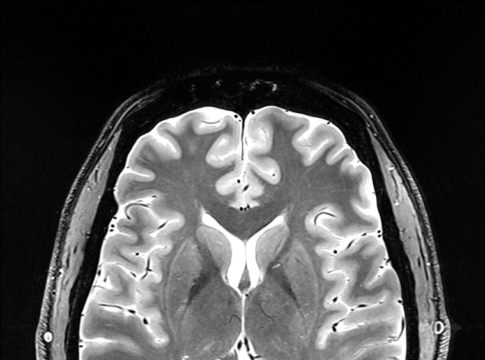

Il est recommandé aux patients ayant obtenu 3 points ou plus de passer une IRM cervicale.